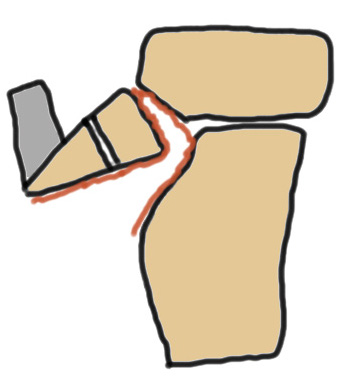

Ogden Classification

A: Undisplaced

B: Displaced

| Type I | Type II | Type III | Type IV |

|---|---|---|---|

| Avulsion distal tibial tubercle | Extension into tibial physis but not into knee joint | Extension across tibial physis and into knee joint | Extends posteriorly across tibial physis |

| Disrupts extensor mechanism | Disrupts extensor mechanism |

Disrupts extensor mechanism Disrupts articular surface Disrupts growth plate |

Disrupts extensor mechanism Disrupts articular surface Disrupts growth plate |

|

Associated Osgood-Schlatter Second most common |

Most common Risk of compartment syndrome |

Risk of compartment syndrome |

Type IB

Type IIB

Type III

Comminuted Type III